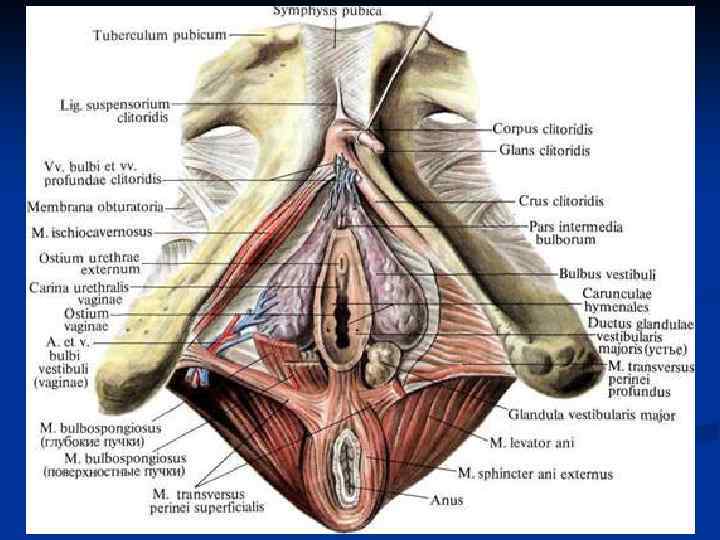

Женские половые органы, organa genitalia feminina

Женские половые органы, organa genitalia feminina